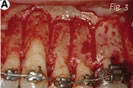

コルチコトミー(皮質骨骨切開術)とは、歯を支える歯槽骨の表面にある骨に少しすじを入れ、歯を動きやすくする方法です。

あごの骨に限らず、骨というのは、外側が非常に固い(皮質骨といいます)のですが、その内部は髄といって血液や柔らかい軟骨で満たされています。またその血液の中には、様々なサイトカインが含まれそれぞれ色々な役割を果たしています。その外側の皮質骨に少量のすじを入れる処置をコルチコトミーと言います。

これらの処置の結果、すじが出来た部分を修復する為に新しい骨の細胞が多数出現してきます。結果として細胞のレベルで代謝が活発になる、また骨の成分が一時的に変化を起こし歯の移動が加速されることが証明されています。

◆ 手術の侵襲量は、成人で中等度以上の歯周病の場合、歯周病治療の為に歯周外科手術や歯周再生治療を行う事がありますが、これらの手術とほぼ同一です。また処置時間は、親知らずを抜くときと同じくらいの処置時間です。術後数日間、歯ぐきと唇周囲の腫れが生じますが、約1種間程度でほぼ傷口は治癒します。

◆ ウェブ上では、コルチコトミーを行うと歯ぐきが痩せる、ブラックトライアングルになるとの情報も多く見受けられます。手術によって歯ぐきが痩せる事や手術によってブラックトライアングルになることはありません。当院で治療をお受けになった方でそのような状況になった方は一人もおりませんので安心してください。当院で用いている手術の術式は、元々歯ぐきや歯の周囲の顎の骨を健康な状況にするために行われる歯周外科術式(歯ぐきへの切開線の入れ方、歯ぐきの剥離の仕方、歯ぐきのフラップの戻し方、縫合法など)を用い、かつ歯周形成外科の術式の一部である歯間乳頭(歯と歯の間の歯ぐき)保存術を採用しています。一方、歯周外科治療に精通していない医師による手術では、危惧されている問題を生じる危険性がありますので、担当医の技量をチェックする必要があります。